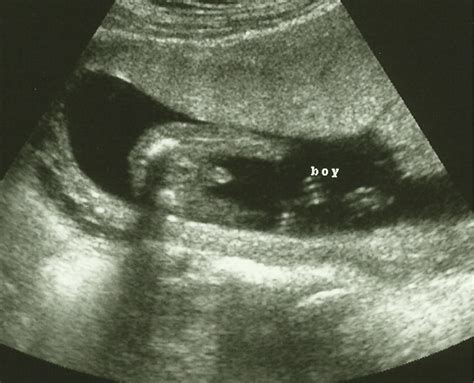

This image is a representation of what you might see during your 20 week ultrasound. The detailed scan provides a clear view of the baby's anatomy, allowing healthcare providers to assess development and identify any potential issues.

Another example of what you might see during your 20 week ultrasound. The scan captures various aspects of the baby's development, including the heart, brain, kidneys, and spine.